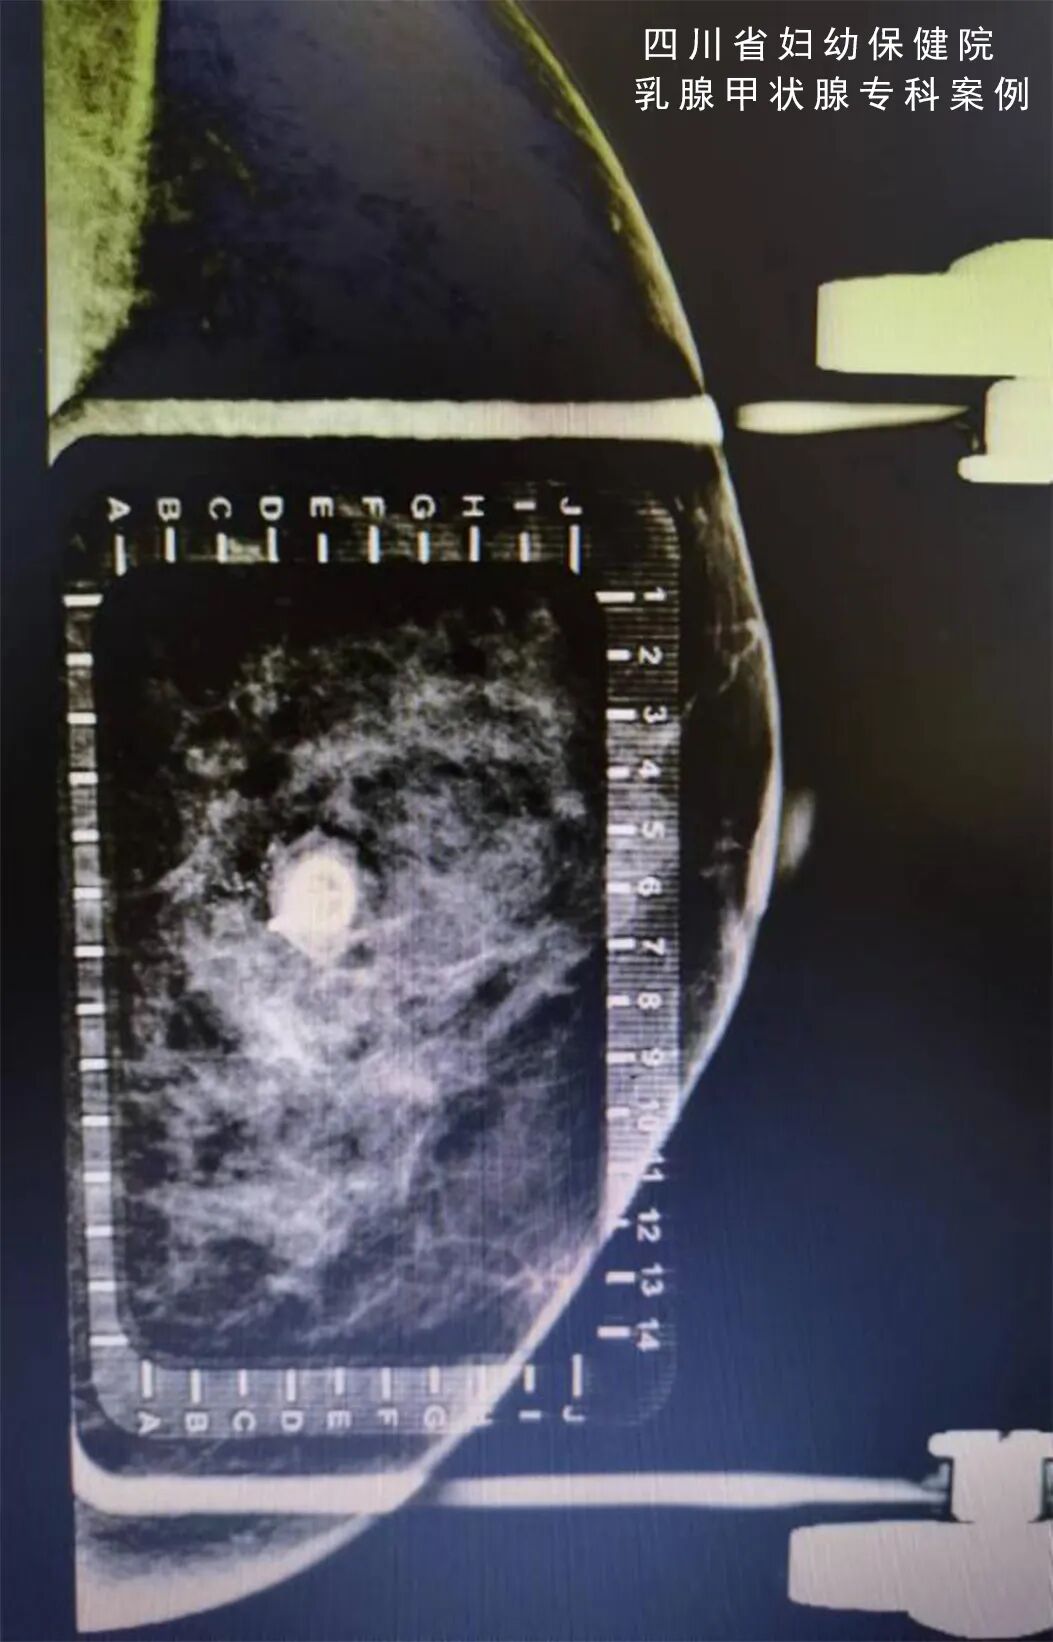

怎么制造手术钩针看医生如何精准“钩出”乳腺钙化灶,将早期乳腺癌“绳之以法”_https://www.jmylbn.com_新闻资讯_第5张

(术中将标本连同钩针一起再次照片确认病灶已切除)